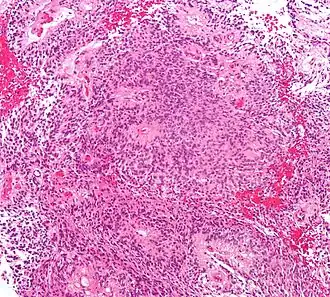

| Histologia do ependimoma (H&E) | |

Ependimomas geralmente são tumores de crescimento lento e mais comuns frequentes em crianças e adultos jovens. São classificados como ependimoma clássico (grau II) e ependimoma anaplásico (grau III) . Estes tumores podem ocorrer em qualquer lugar do sistema ventricular ou do canal espinal, entretanto são mais comuns no quarto ventrículo e no canal espinal. Ependimomas são geralmente bem demarcados e com frequentes áreas de calcificação, hemorragia e eventualmente cistos., as células tumorais frequentemente formam as chamadas rosetas ependimais, sinais que praticamente selam o diagnóstico.